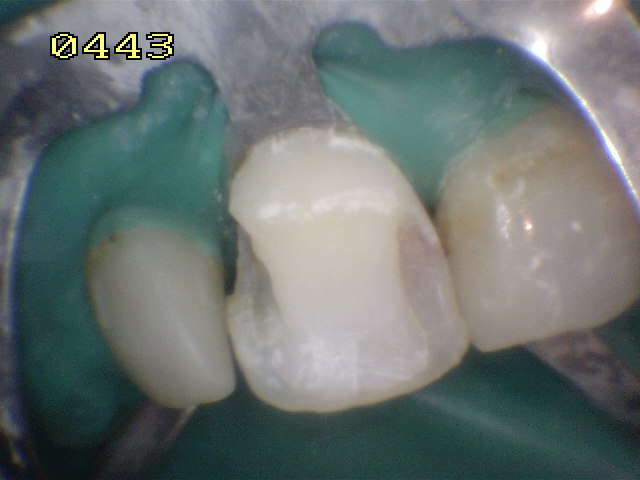

Se elimina el material y

tejido cariado, con un rebaje de la cara vestibular |